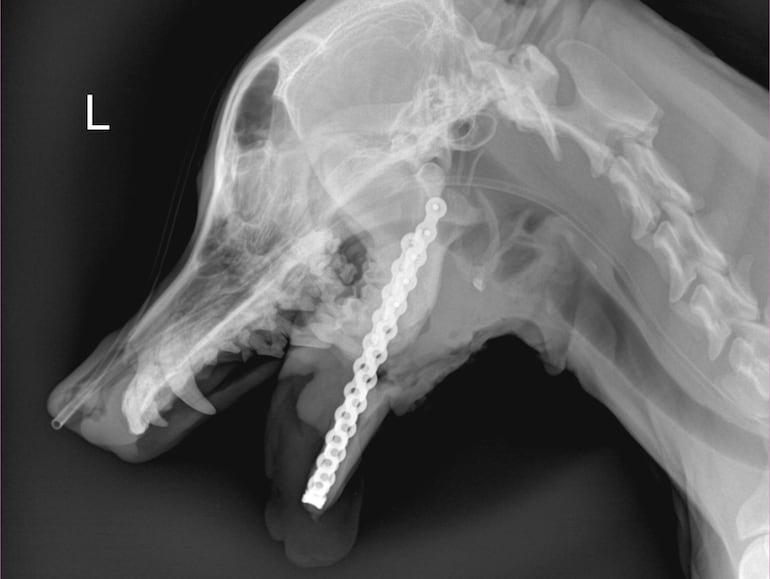

La perrita sobrevivió al hecho tras una delicada cirugía y luego de pasar varias semanas en un hogar temporal, hoy fue sometida a otra intervención para recuperar su mandíbula mediante una prótesis.

La organización Olfateando Huellas fue la que compartía constantemente actualizaciones sobre su estado y hoy confirmó que la cirugía fue un éxito y también celebró este hecho abre la oportunidad de otros procedimientos similares.

“Histórico. Hoy nace una nueva oportunidad para todos los animales del Paraguay. La cirugía fue un éxito total; logramos devolverle a Canela su mandíbula”, publicaron en redes sociales. El equipo médico que realizó la cirugía estuvo compuesto por los doctores Lourdes Natalie Servín, Mercedes Martínez, Pedro Luis Ferrer, Fabricio Ferrer, Deydra Valenzuela, Mario Borba, Yanina Sambrini y la licenciada Raquel Núñez.